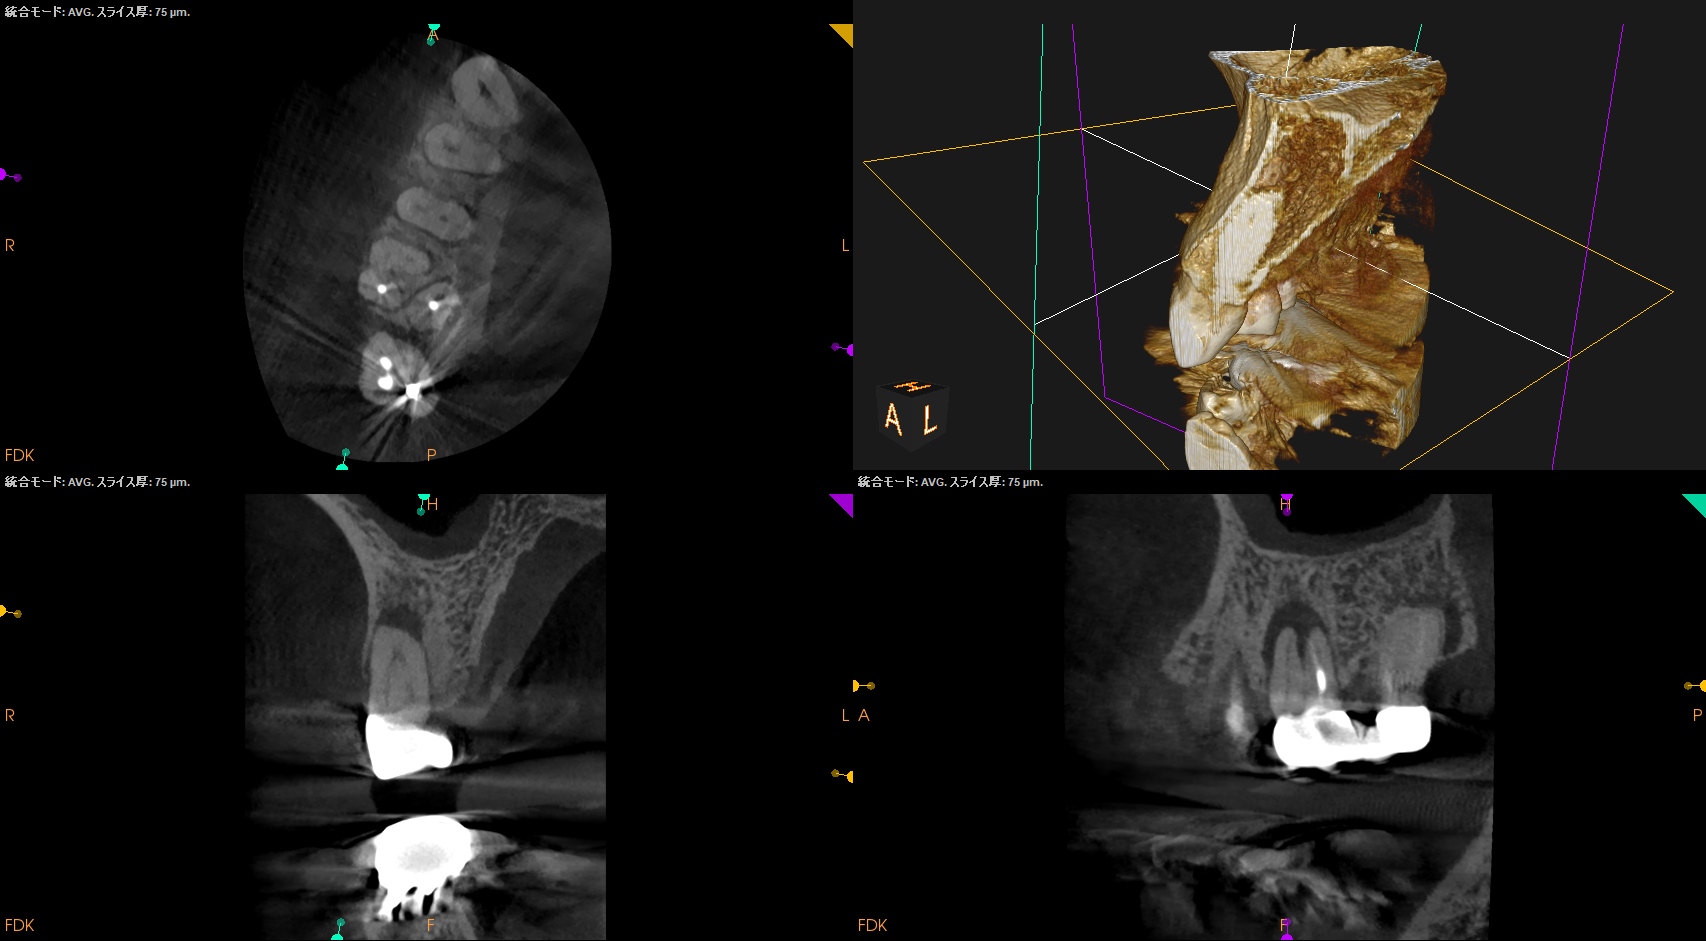

#3 MB,DB Apicoectomy 1yr recall(2025.12.24)

術前のSinus tract・臨床症状(根尖部圧痛)も術後の縫合の傷跡もない。

MB

DB

B

外科治療の際に開創した歯槽骨は再生した。

術前と比較した。

問題は消失した。

MBは根尖部の形成は穿孔しているだろうが即座に穿孔封鎖したから=即座に逆根充したから問題が起きていない。

ということで完治したのでこの日で終診とさせていただいた。